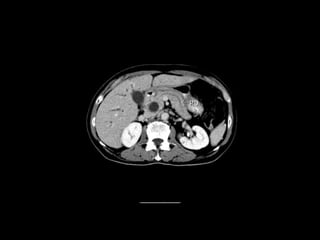

Radiographers use medical imaging equipment like X-rays and MRIs to produce images of patients' internal structures and organs. They are responsible for positioning patients, operating scanning machines, and ensuring quality images. Radiographers must have strong attention to detail, excellent communication skills, and the ability to work well under pressure to accurately capture anatomical features and diagnose any abnormalities.